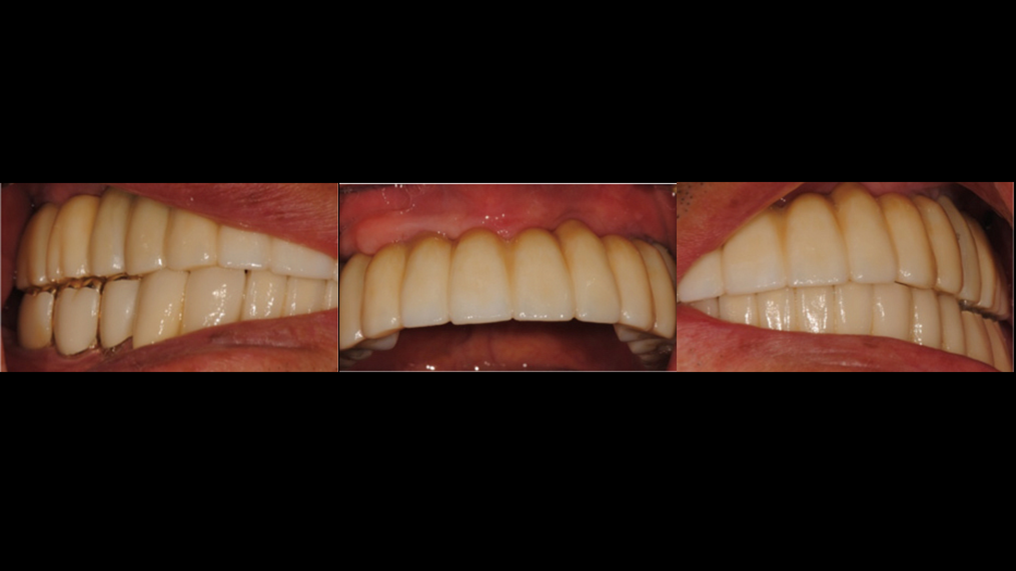

Clinical case: A Full transition from natural teeth to all-on-6 bridges

with AnyRidge implants

- Courtesy of Dr. Rabih Abi Nader, UAE -

Keywords

Full-mouth rehabilitation, minimal layering, Zirconia, all-on-6, life changing result, edentulous ,Dr. Rabih Abi Nader, AnyRidge

Products:

AnyRidge implant system